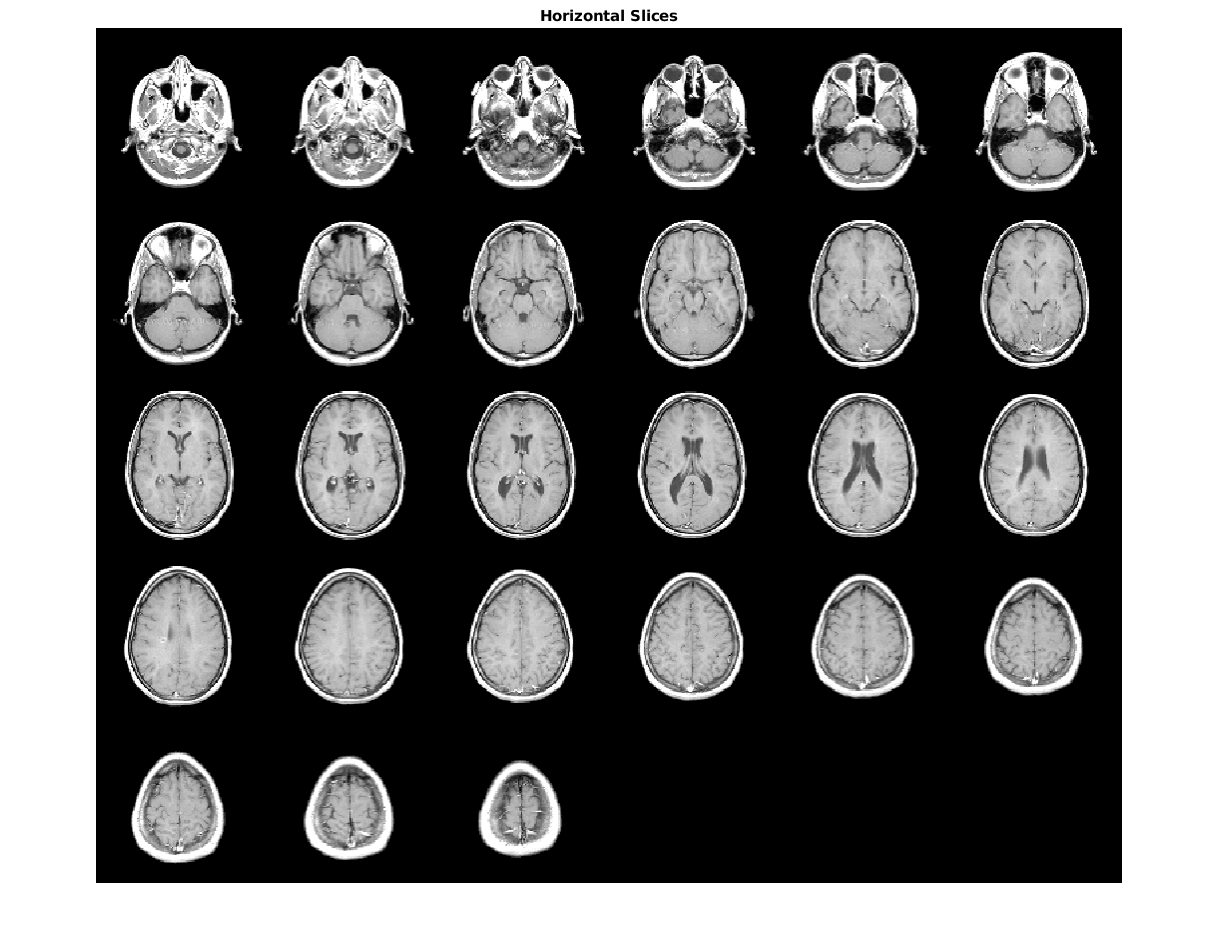

Slices contains

Slices contains 142 фотографий